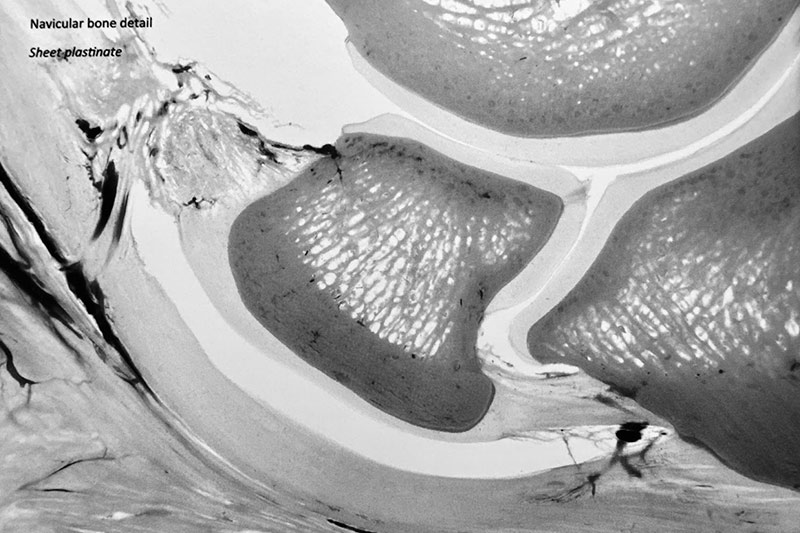

© Dr. Christoph von Horst

Navicular syndrome, also known as navicular disease, is a chronic and progressive condition affecting the navicular bone and associated structures in a horse's hoof. This small, boat-shaped bone located in the horse's foot plays a crucial role in proper limb function and movement. When this bone and the surrounding tissues become damaged or inflamed, it can lead to significant pain and lameness. The exact causes of navicular syndrome can vary, but it is generally understood to be the result of a combination of genetic, biomechanical, and environmental factors.